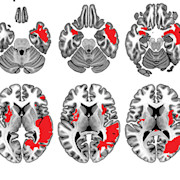

“Cyclic variations of estrogen and progesterone levels are known to affect women’s emotion recognition, and influence activity and connections in associated brain regions. Since oral contraceptives work by suppressing estrogen and progesterone levels, it makes sense that oral contraceptives also affect women’s emotion recognition However, the exact mechanism underlying oral contraceptive induced changes in women’s emotion recognition remains to be elucidated.”